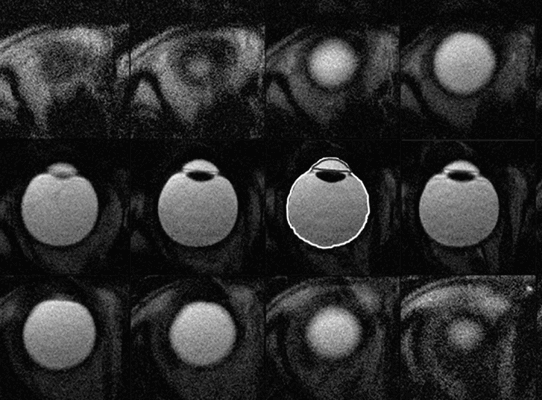

Тот же пациент, исследование в динамике через 4,5 года

Исследование в 2008 году Исследование в 2013 году